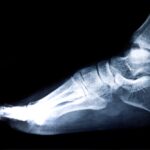

- Imaging tests like X-rays, CT scans, or MRIs.